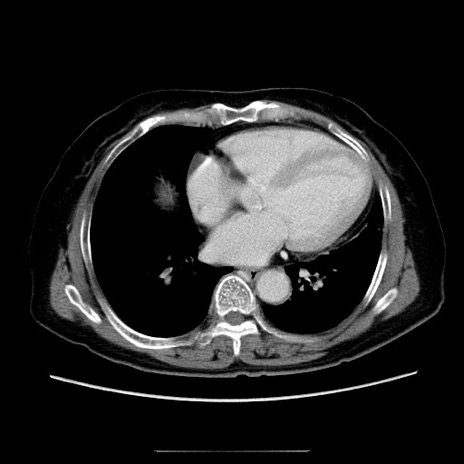

症例5(横断像)

【症例】70歳代女性

【主訴】お腹が張る

【現病歴】1週間くらい前から腹部膨満の自覚あり。昨日夜から増悪したため、本日救急外来受診。

【身体所見】意識清明、BT 36.5℃、BP 165/106mmHg、HR 80bpm、SpO2 98%、腹部:膨満、軟、自発痛・圧痛なし、触診にて不快感あり、腸蠕動音:減弱

【データ】WBC 12600、CRP 1.04